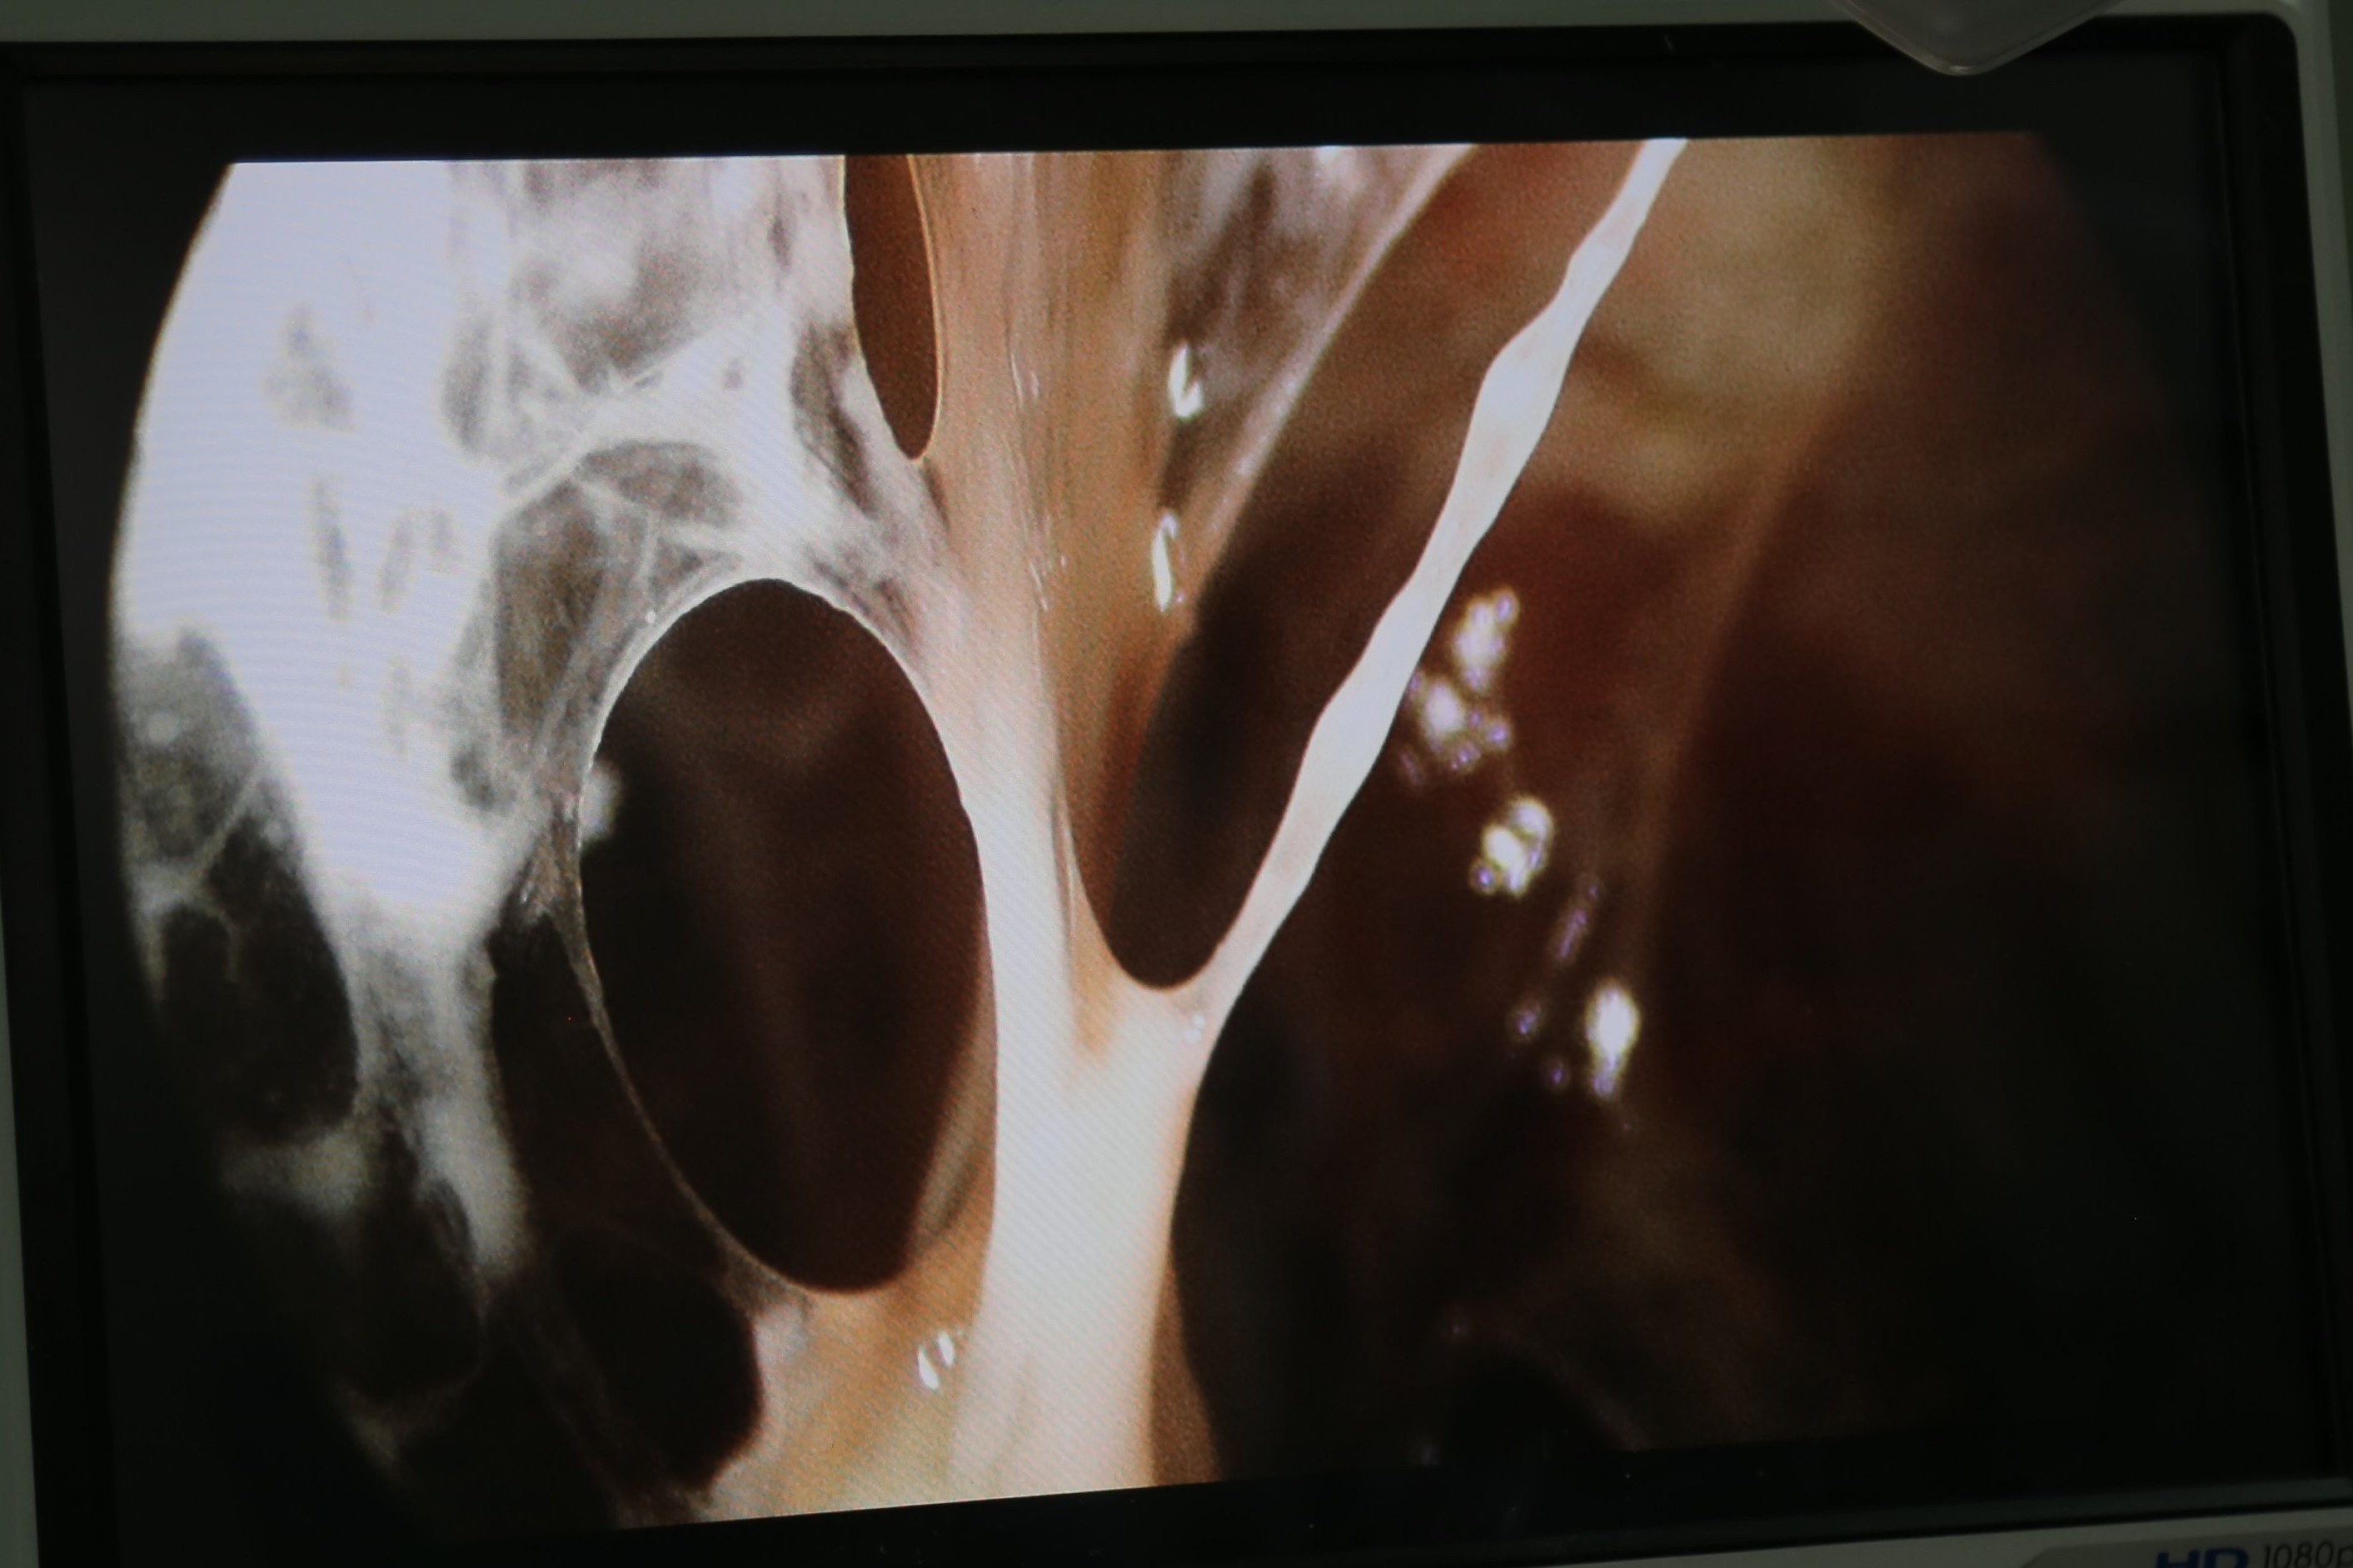

Phổi bệnh nhân xuất hiện nhiều dịch nhầy. Ảnh: BVCC.

Sau khi chụp CT màng phổi, các bác sĩ nhận thấy tình trạng đông đặc, viêm dính rất nhiều ở nhu mô phổi. Từ đây, ông được chuyển tới khoa Truyền nhiễm điều trị nội trú.

Sau một tuần, kết quả chụp CT ngực cho thấy phần phổi xẹp có phục hồi tương đối. Tuy nhiên, ổ áp xe chưa được dẫn lưu hoàn toàn, vẫn còn nhiều mủ đọng ở lá tạng. Đồng thời, sau giai đoạn viêm mủ, 2 màng phổi có những chỗ dày lên và dính lại với nhau, khiến chức năng hô hấp bị ảnh hưởng và tạo thành các khoang bên trong, việc dẫn lưu dịch và khí trong khoang màng phổi không còn hiệu quả.